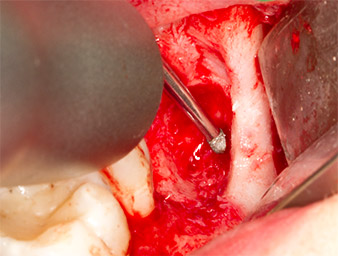

Con el fin de obtener material autógeno para el tratamiento posterior de la herida, se utilizó un inserto piezoquirúrgico (Piezomed B5) para obtener virutas de hueso sano del entorno del resto radicular (figura 5).

Piezomed B5

Imagen 5: Con un inserto piezoquirúrgico con forma de cincel (Piezomed B5) se eleva el hueso en el área de los alvéolos. Tras la retirada del resto radicular, este sirve como material de aumento autólogo (véase figuras 13 y 14).

El tejido autógeno se extrajo con la punta de trabajo en forma de pala del inserto y se guardó en solución salina fisiológica hasta su posterior utilización (véase figura 13).